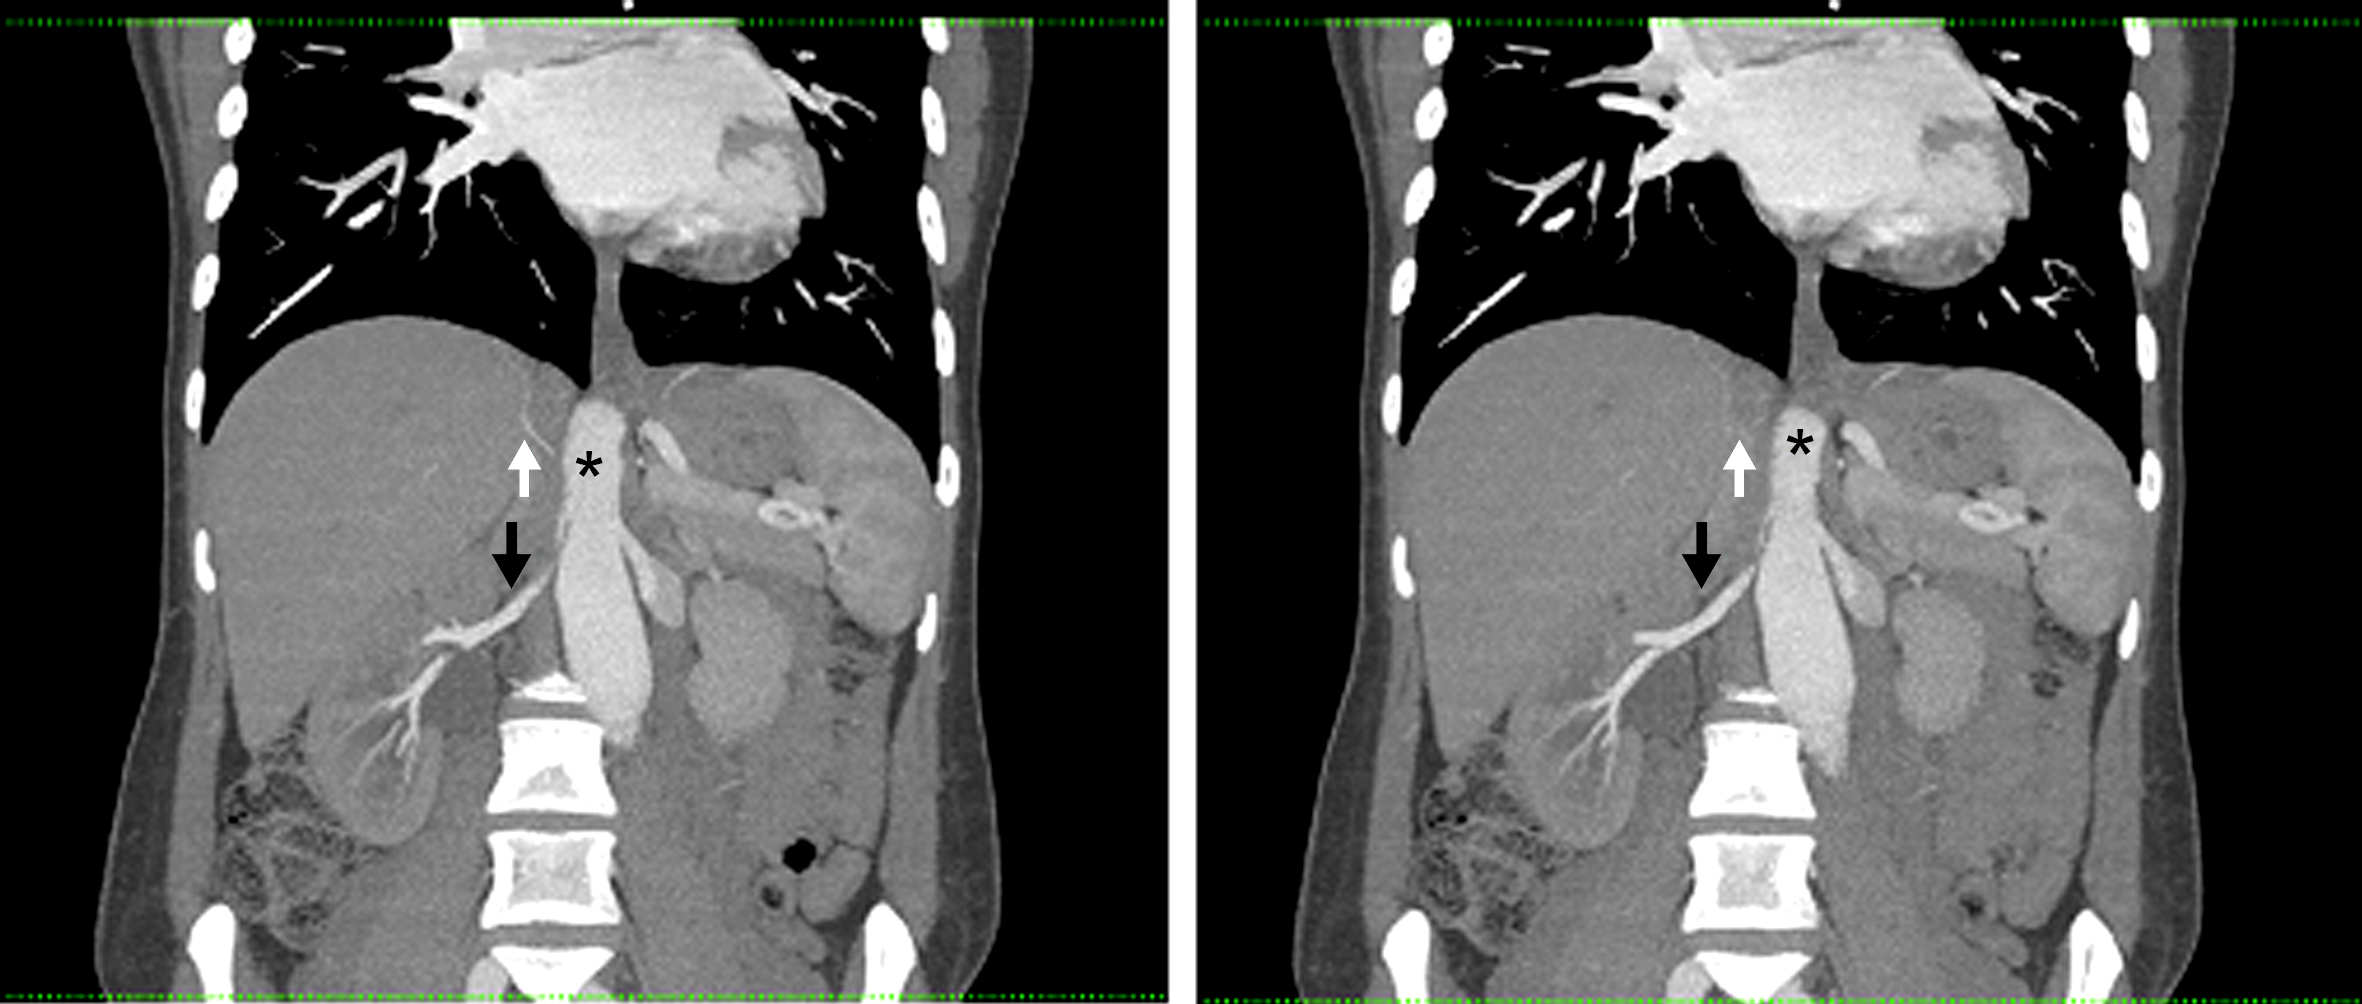

Figura 2

Angiografía de Aorta por TC Proyección de máxima intensidad. Cortes coronales. (*) Aorta abdominal, (flecha blanca) Crura diafragmática derecha, (flecha negra) Arteria renal derecha.

La arteria renal derecha es única, se encuentra permeable, y presenta franca disminución de su calibre y trayecto “verticalizado” en su sector proximal, transcurriendo entre la aorta abdominal y la crura diafragmática ipsilateral en su segmento inicial. Distalmente la arteria renal derecha presenta calibre normal, de aprox. 6 mm de diámetro. Así mismo se observa realce asimétrico de ambos riñones tras la administración de medio de contraste i/v, evidenciándose menor captación del mismo en forma difusa a derecha (nefrograma tardío) en comparación con el riñón contralateral, lo cual traduce hipoperfusión renal. (Figs. 1 y 2)

El tronco celíaco y la arteria mesentérica superior se encuentran permeables y de calibre habitual. Se identifica un origen alto de las ramas viscerales de la aorta abdominal, a saber, el tronco celíaco a la altura del espacio discal T11-T12, la arteria mesentérica superior a nivel del cuerpo vertebral de T12, la arteria renal derecha a nivel del espacio T12-L1 y de la arteria renal izquierda a nivel del margen superior de cuerpo de L1. (Fig. 3)

Por último destacamos la presencia de un útero grávido con feto en su interior, antecedente que ya conocíamos. Los hallazgos descritos son compatibles con el planteo de Síndrome de atrapamiento de la arteria renal derecha por la crura diafragmática.